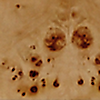

Complemented by clean lines and a minimal design, active burl wood veneer is the star of this console table designed by VUUE. Thick rectangular legs stand flush with the top, providing structural interest without distracting from the wood's gorgeous swirling grain. CB2 exclusive.

• Engineered wood frame with burl wood veneer

• Variation in burl wood to be expected; each piece will be unique